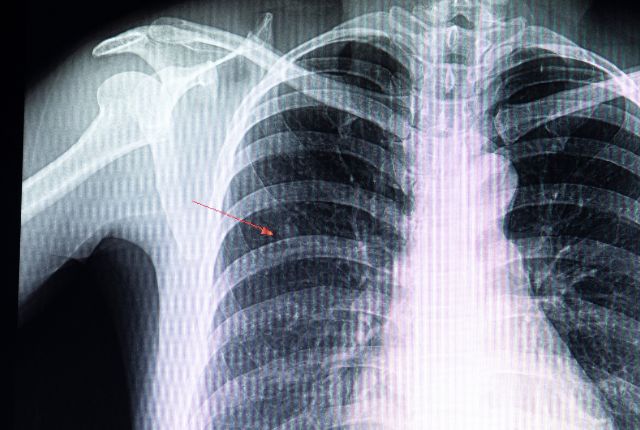

Atélectasie pulmonaire remèdes naturels: L’atélectasie pulmonaire est une affection respiratoire qui se caractérise par l’affaissement d’une partie du poumon, réduisant ainsi le volume d’air disponible pour la respiration. Bien que la circulation sanguine demeure intacte, cette diminution d’oxygénation peut entraîner divers inconforts respiratoires. Heureusement, des solutions naturelles existent pour favoriser une meilleure respiration et prévenir cette condition.